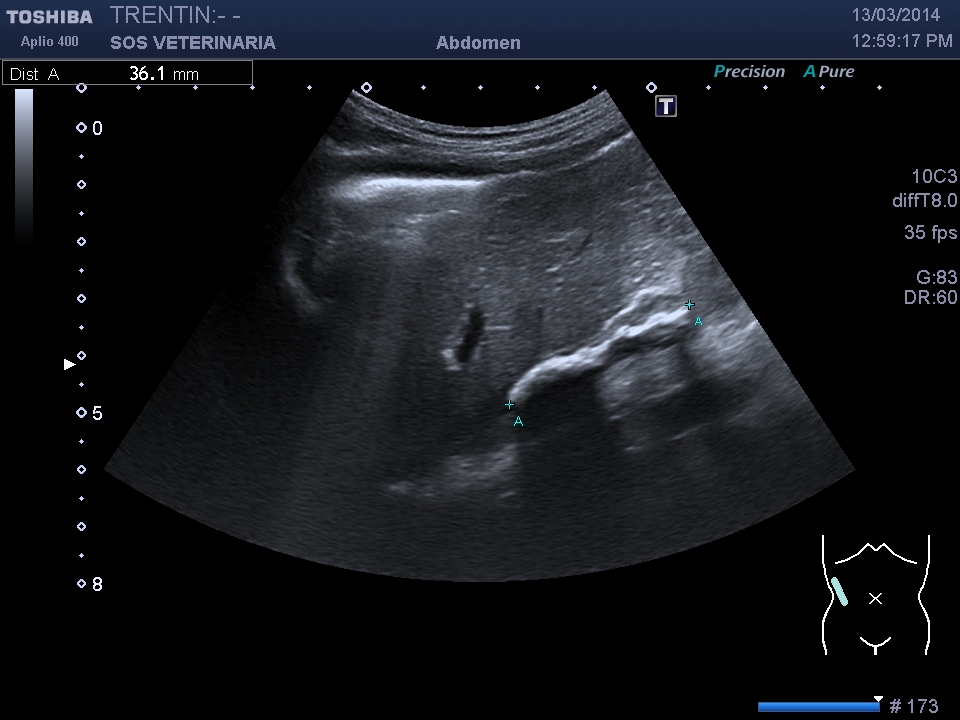

massa surrenalica e invasione cavale

massa surrenalica